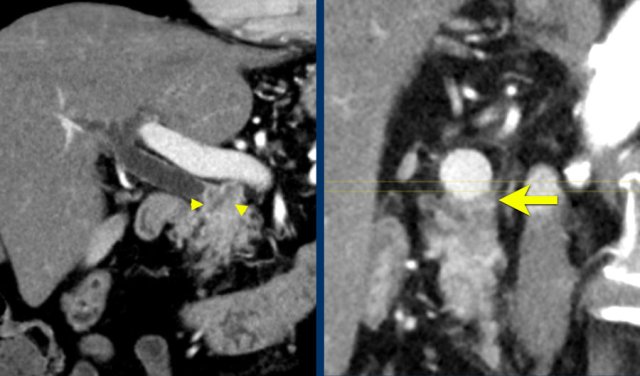

Vessel irregularity

Axial CT shows:

- Tumor in the body of the pancreas (white arrowhead).

- Focal < 90º contact with the SMA.

- More extensive 90º – 180º contact with the SMV , which is slightly narrowed and deformed (yellow arrow).

- Dilatation of the pancreatic duct

The coronal reconstruction shows:

- Vessel wall irregularity of the SMV is better appreciated on this coronal reformat (arrow).

- Thrombosis in SMV side branches (small green arrows).